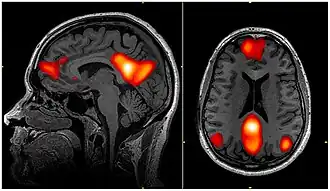

![]() Imagem de fMRI mostrando regiões da rede de modo padrão |

Na neurociência, a rede de modo padrão (DMN, do inglês Default Mode Network, ou RMP), também rede padrão, ou rede cerebral padrão, é uma rede cerebral de larga escala de regiões do cérebro em interação, conhecidas por terem atividade altamente correlacionada entre si e distinta de outras redes no cérebro.[3]

Foi inicialmente assumido que a rede de modo padrão estaria mais comumente ativa quando uma pessoa não está focada no mundo exterior e o cérebro está de repouso mas em vigília, como ao "sonhar acordado" e durante divagação mental. No entanto, agora se sabe que ela pode contribuir para elementos da experiência relacionados ao desempenho de tarefas externas.[4] Também é ativa quando o indivíduo está pensando nos outros, pensando em si mesmo, lembrando-se do passado e planejando o futuro.[3][5] Embora a DMN tenha sido originalmente observada como estando desativada em certas tarefas orientadas a objetivos e às vezes seja chamada de rede negativa à tarefa (task-negative),[6] ela pode estar ativa em outras tarefas orientadas a objetivos, como memória de trabalho social ou tarefas autobiográficas.[7] A DMN demonstrou estar correlacionada negativamente com outras redes no cérebro, como as redes de atenção.[8]